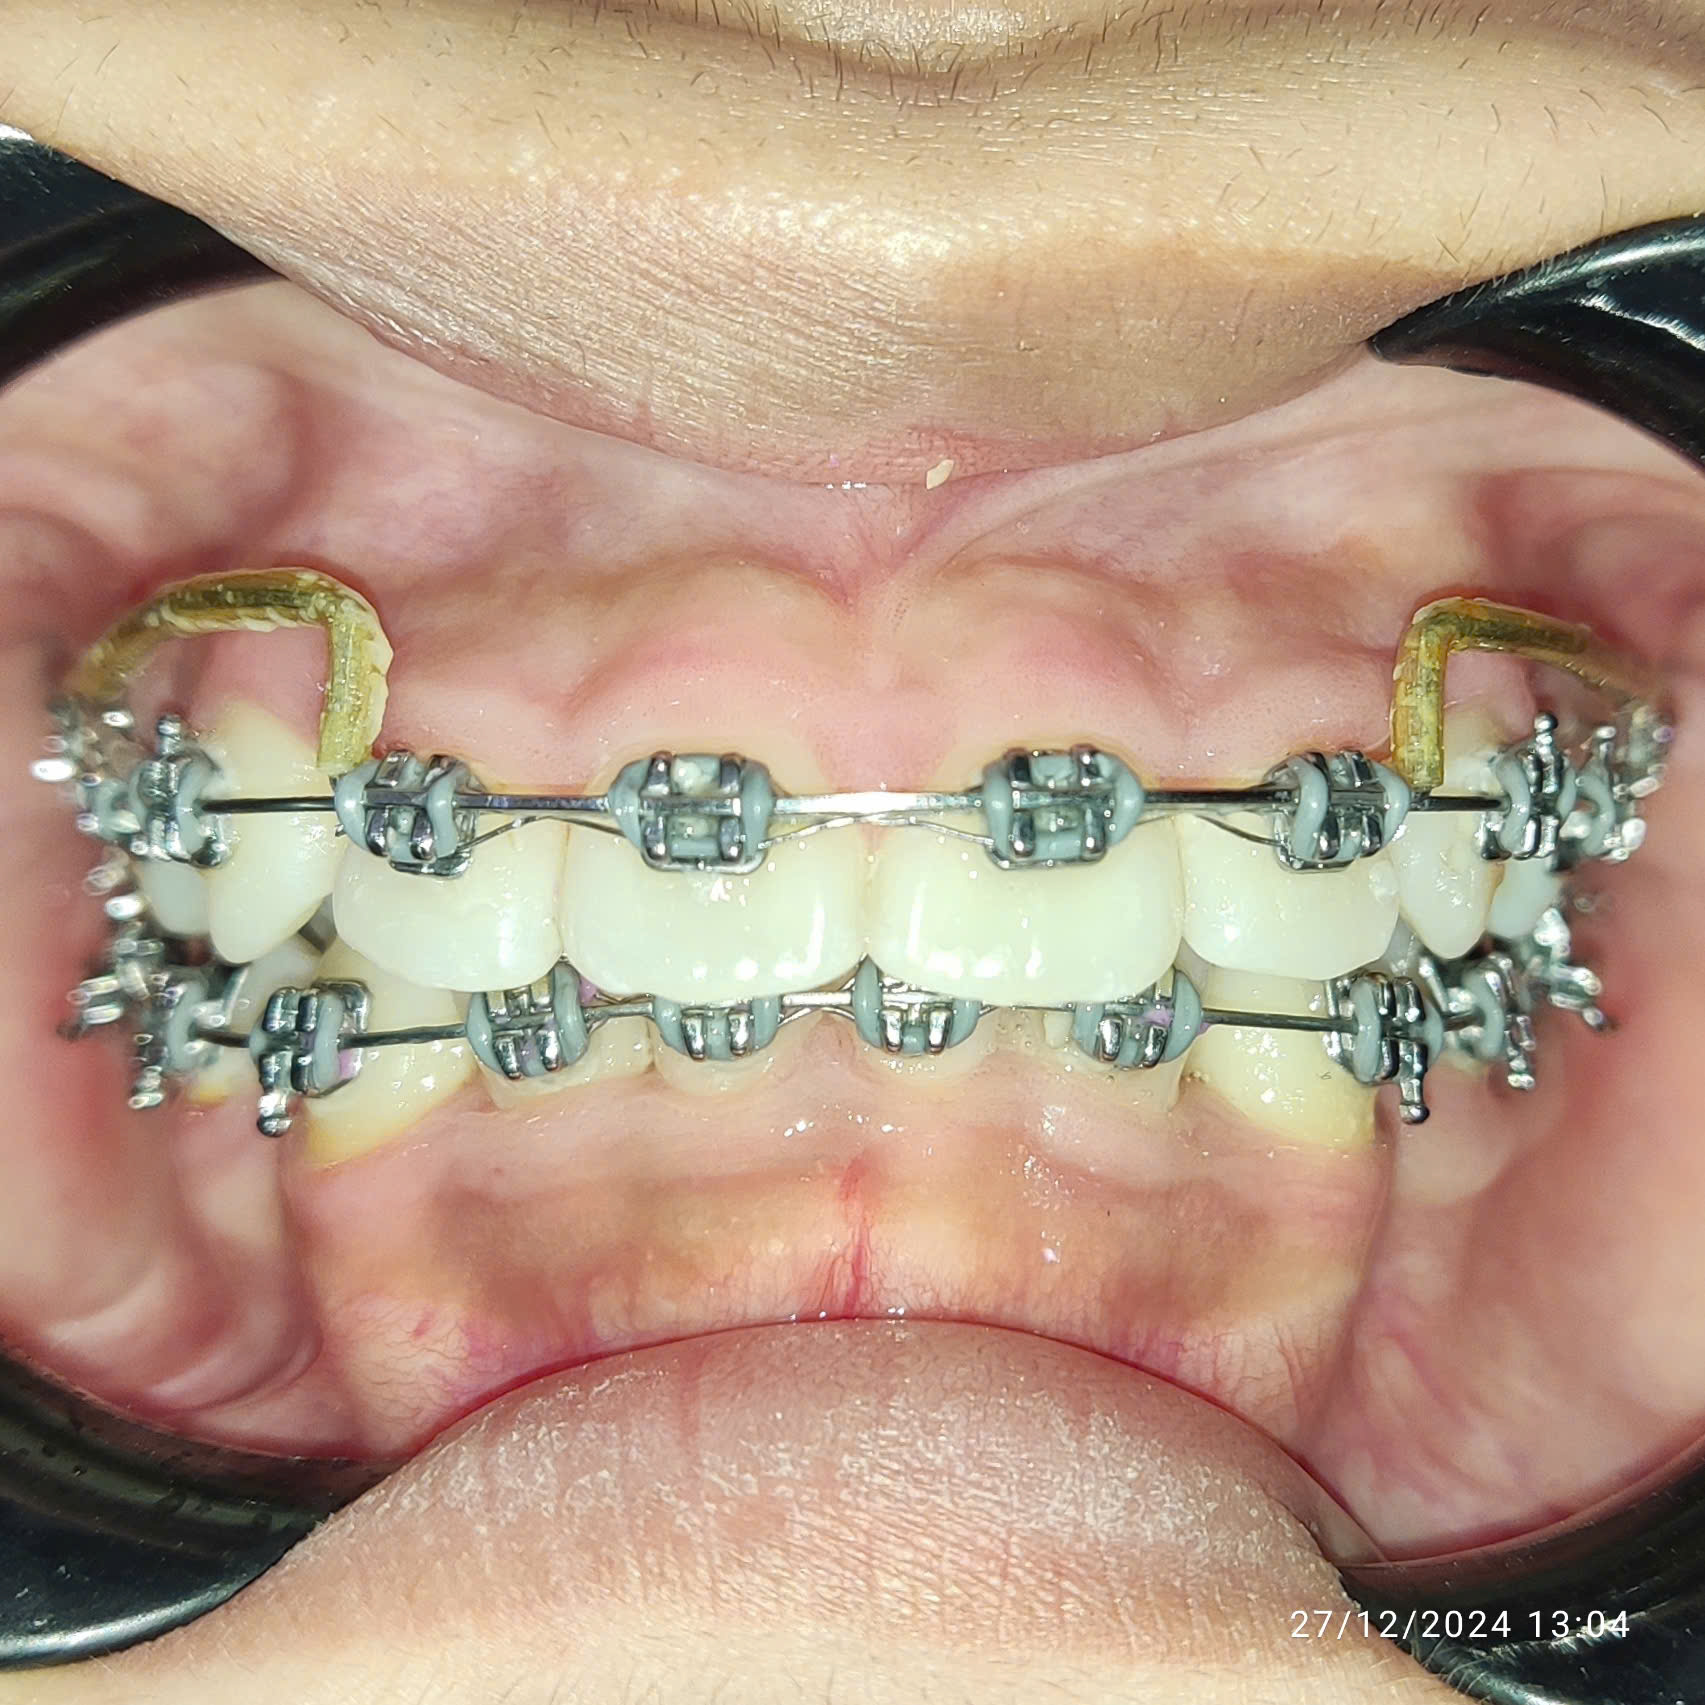

Khách hàng sau điều trị

Thấy con tự ti vì răng khấp khểnh, ba mẹ của Khánh Linh đã đưa bạn đến thăm khám và lựa chọn niềng răng tại Nha khoa Việt Mỹ.. Nhờ can thiệp kịp thời ngay ở độ tuổi vàng, chỉ sau hơn 1 năm, tình trạng răng của Khánh Linh đã được cải thiện rõ rệt khi răng dần dịch chuyển đúng vị trí, gương mặt của con cũng hài hòa hơn.